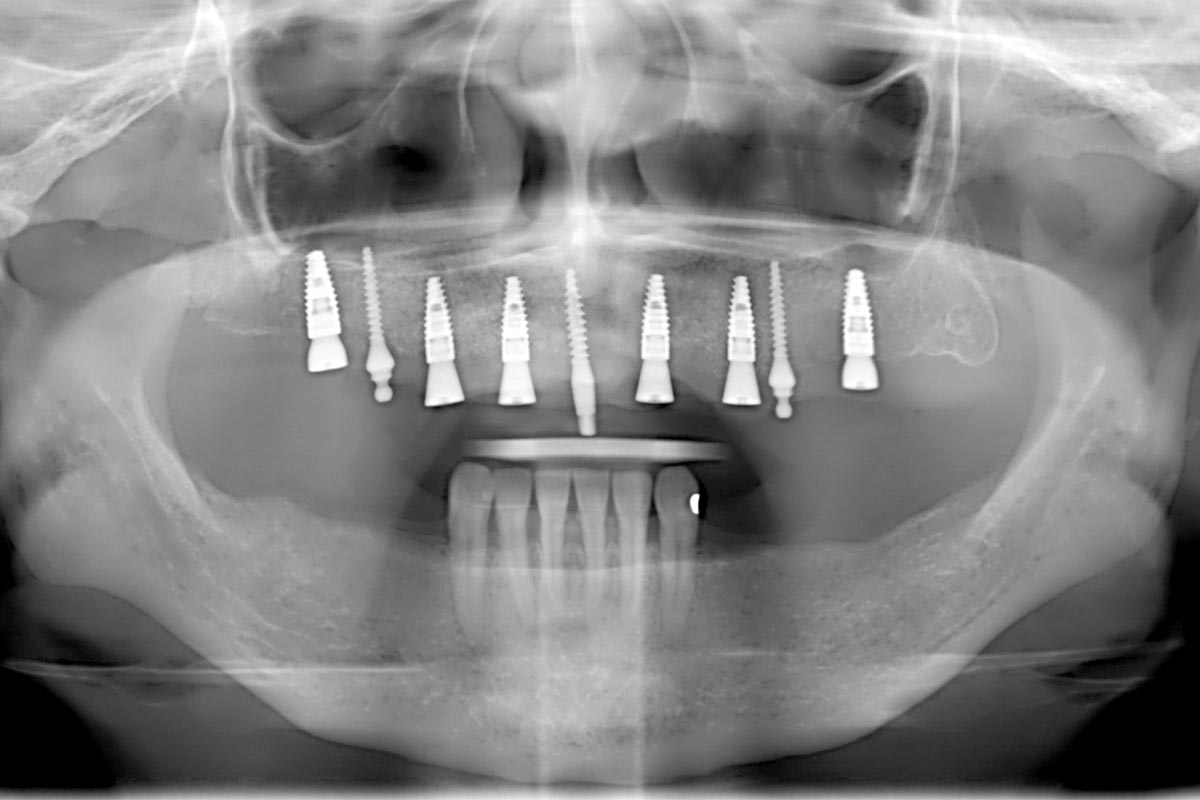

Initial x-ray showing bone loss around implants placed 5 years ago in another dental clinic